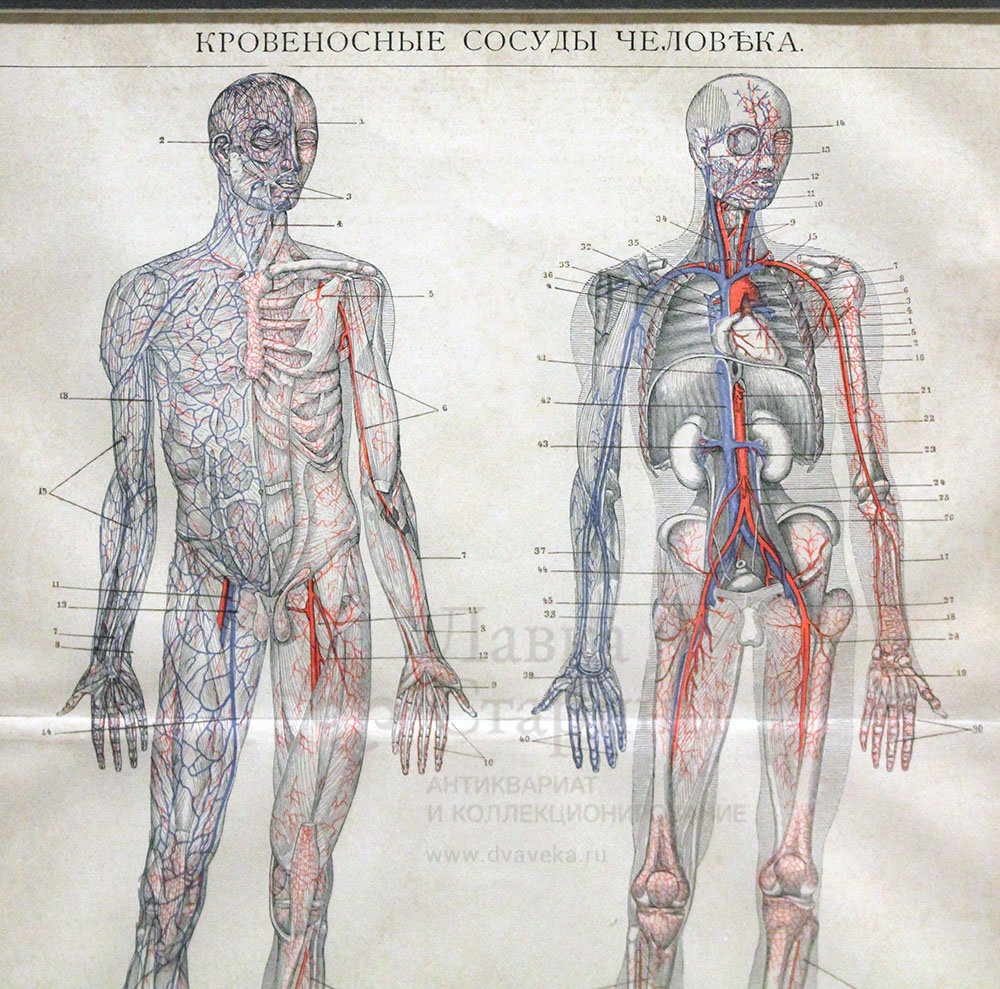

Анатомия человека: кровеносная система и её связь со скелетом